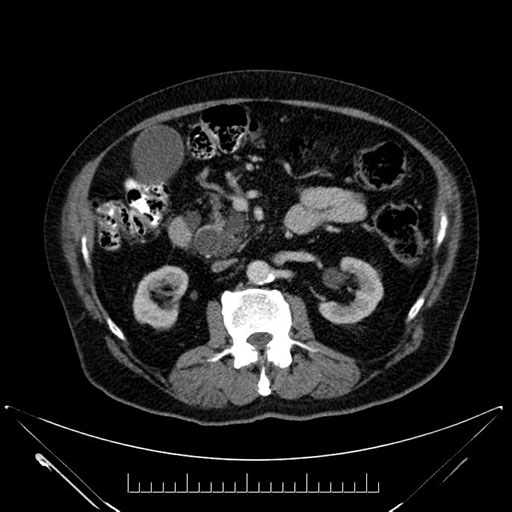

Whipple (pancreaticoduodenectomy) [case 7]

Axial - stented